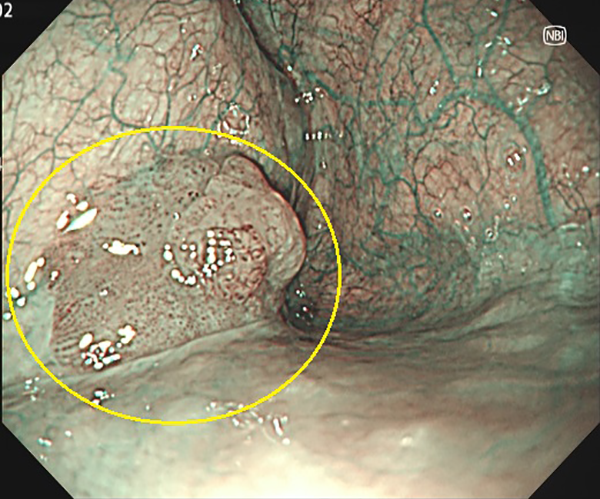

⑤大腸がん(側方発育型腫瘍(LST))

1. 大腸ポリープ既往歴があり、定期的検査として内視鏡検査を施行、横行結腸に10mm強の表面比較的平滑な扁平隆起を認めます。

2. NBI画像処理で表面構造の異常(周辺が均一な小円形構造に対し、不均一)を認めます。側方発育型腫瘍(非顆粒型)であり内視鏡的粘膜切除術で治癒、粘膜内癌と診断されました。